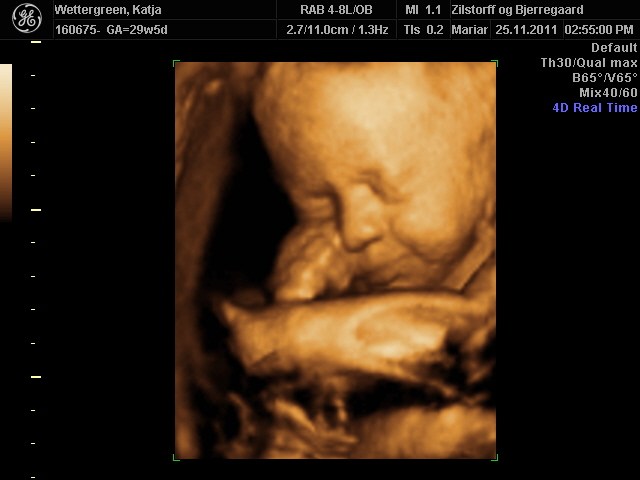

Her går det også godt, - er lige kommet hjem fra en fantastisk 3D scanning. Vores lille pige har det godt og er helt igennem fin! SÅ SØD! Hun har indhentet den manglende vægt og ligger nu lige over gennemsnittet med ca. 1500 g, så det er dejligt!

Jeg er blevet sygemeldt grundet lavt blodtryk, og jeg tror at dette også har haft en positiv indvirkning på hendes vægt. På mandag skal vi til vækstscanning på Hvidovre, - så må vi se om de er enige.